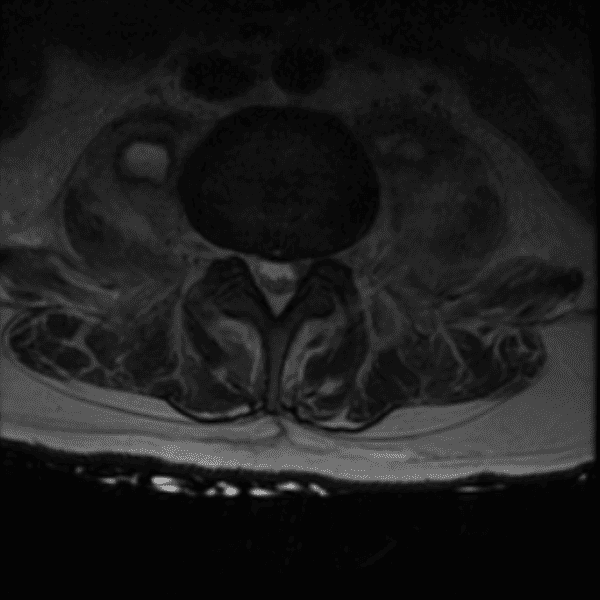

Simulates call by including subtle or difficult cases and some normals.

35 cases